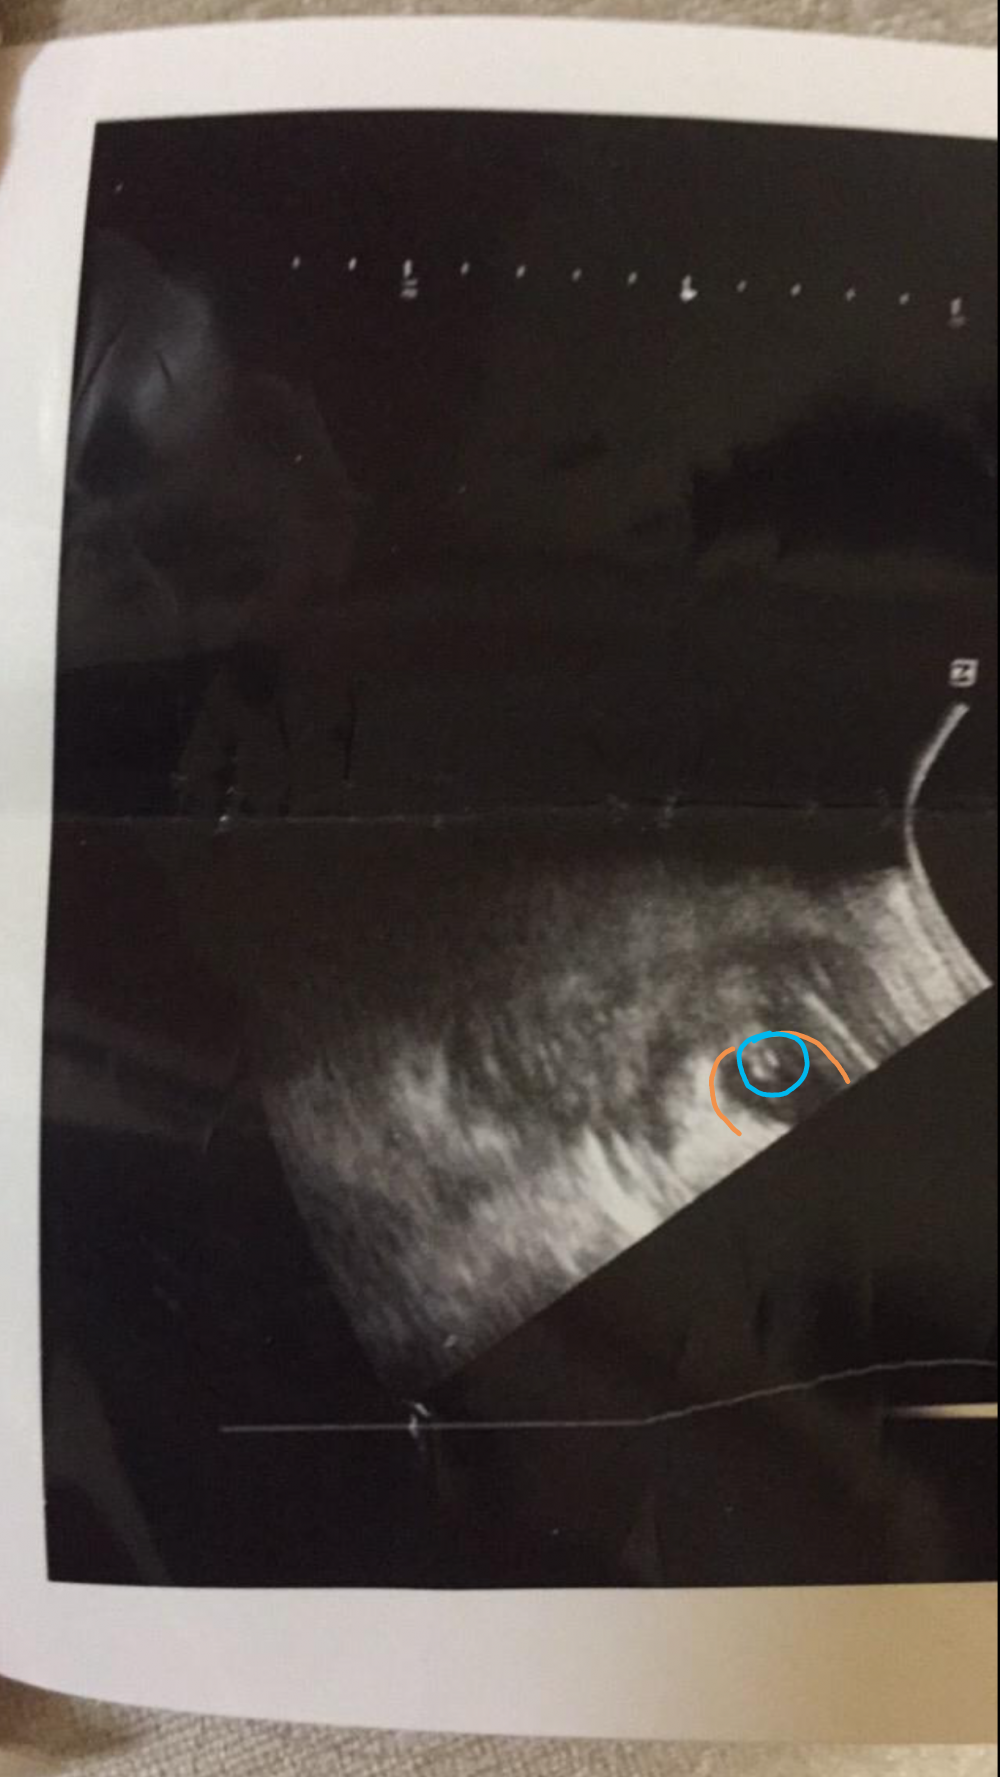

سوناري بنات علموني شتشوفون ان شاء الله يكون واضح

رووز حسب خبرتي المحدوده من اللي تعلمته فالنت ان اللي لونته بالبرتقالي هم الرجلين وواضح العضو فالدايره الزرقا

حتى مبين برووزه شوفي واضح فالمنطقه السوده بين الرجول